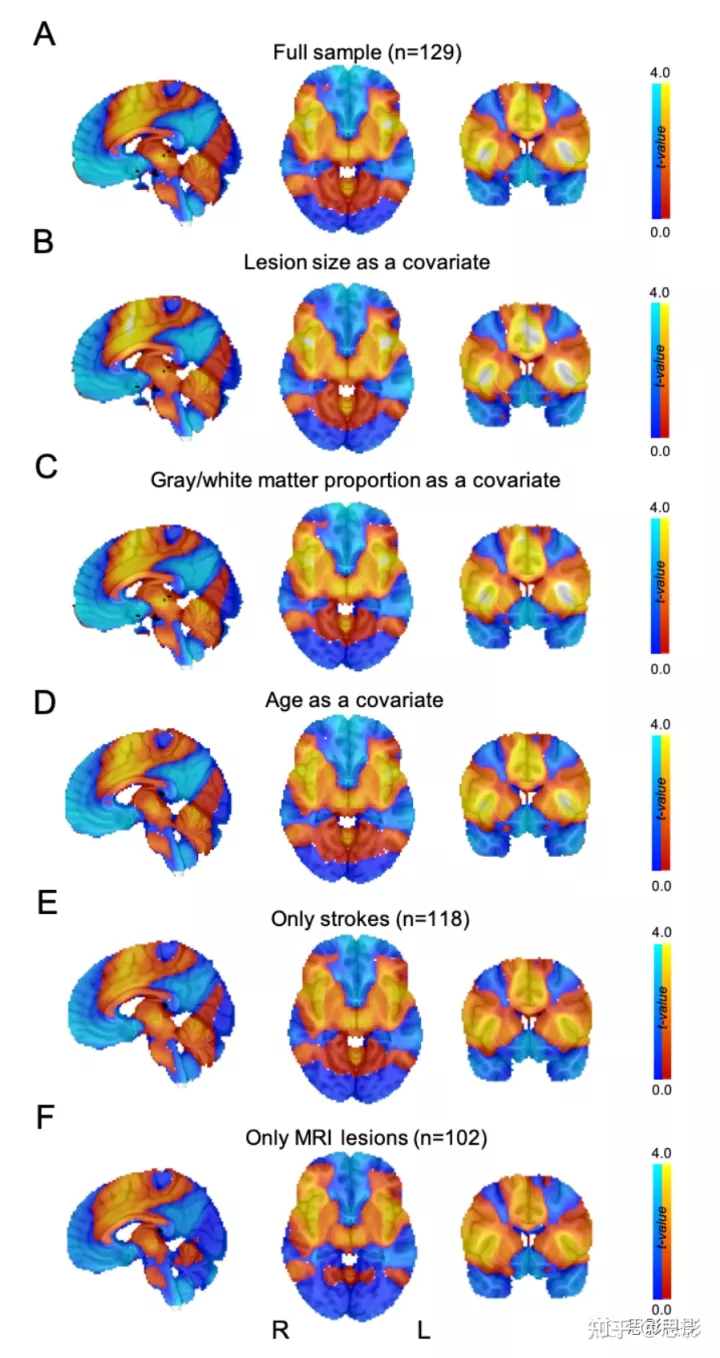

当使用我们的2个独立病变组单独计算时,这种连接模式是可重现的(空间相似性 r = 0.58,置换检验 P = 0.03;补充图 3);与组间成瘾缓解相关( P = 0.04);并且由破坏吸烟成瘾的病变之间的相似性驱动,而不是来自非戒烟者的病变之间的相似性(U = 694,P <0.001;补充材料图4)。连接模式对于定义每日主动吸烟的不同截止值是稳健的(见补充材料图5),将病变大小添加为协变量(见补充材料图6),添加病变掩模中灰质/白质的比例作为协变量(见补充材料图6c),添加患者年龄作为协变量(见补充材料图6d),将我们的分析限制为仅中风(见补充材料图6e),将我们的分析限制在使用磁共振成像(magnetic resonance imaging, MRI)定义的病变掩模上(见补充材料图6f),使用未经全局信号回归处理的连接组(见补充材料图7)或者在中介分析中以岛叶损伤作为协变量(见补充材料图8)。

图 S6:成瘾缓解网络结果对方法选择具有鲁棒性。

当包括病变大小(B)、病变中灰质/白质的比例(C)或患者年龄(D)作为协变量时,不包括中风以外的病变(E),或仅包括有 MRI 的病变患者(F),我们的主要分析(A)的成瘾缓解网络图保持不变。地图未设置阈值以方便比较。我们原始的成瘾缓解网络图(A)与 B、C、D、E 和 F 中的图之间的空间相关系数分别为 r=0.99、r=0.99、r=0.999、r=0.98 和 r=0.94。